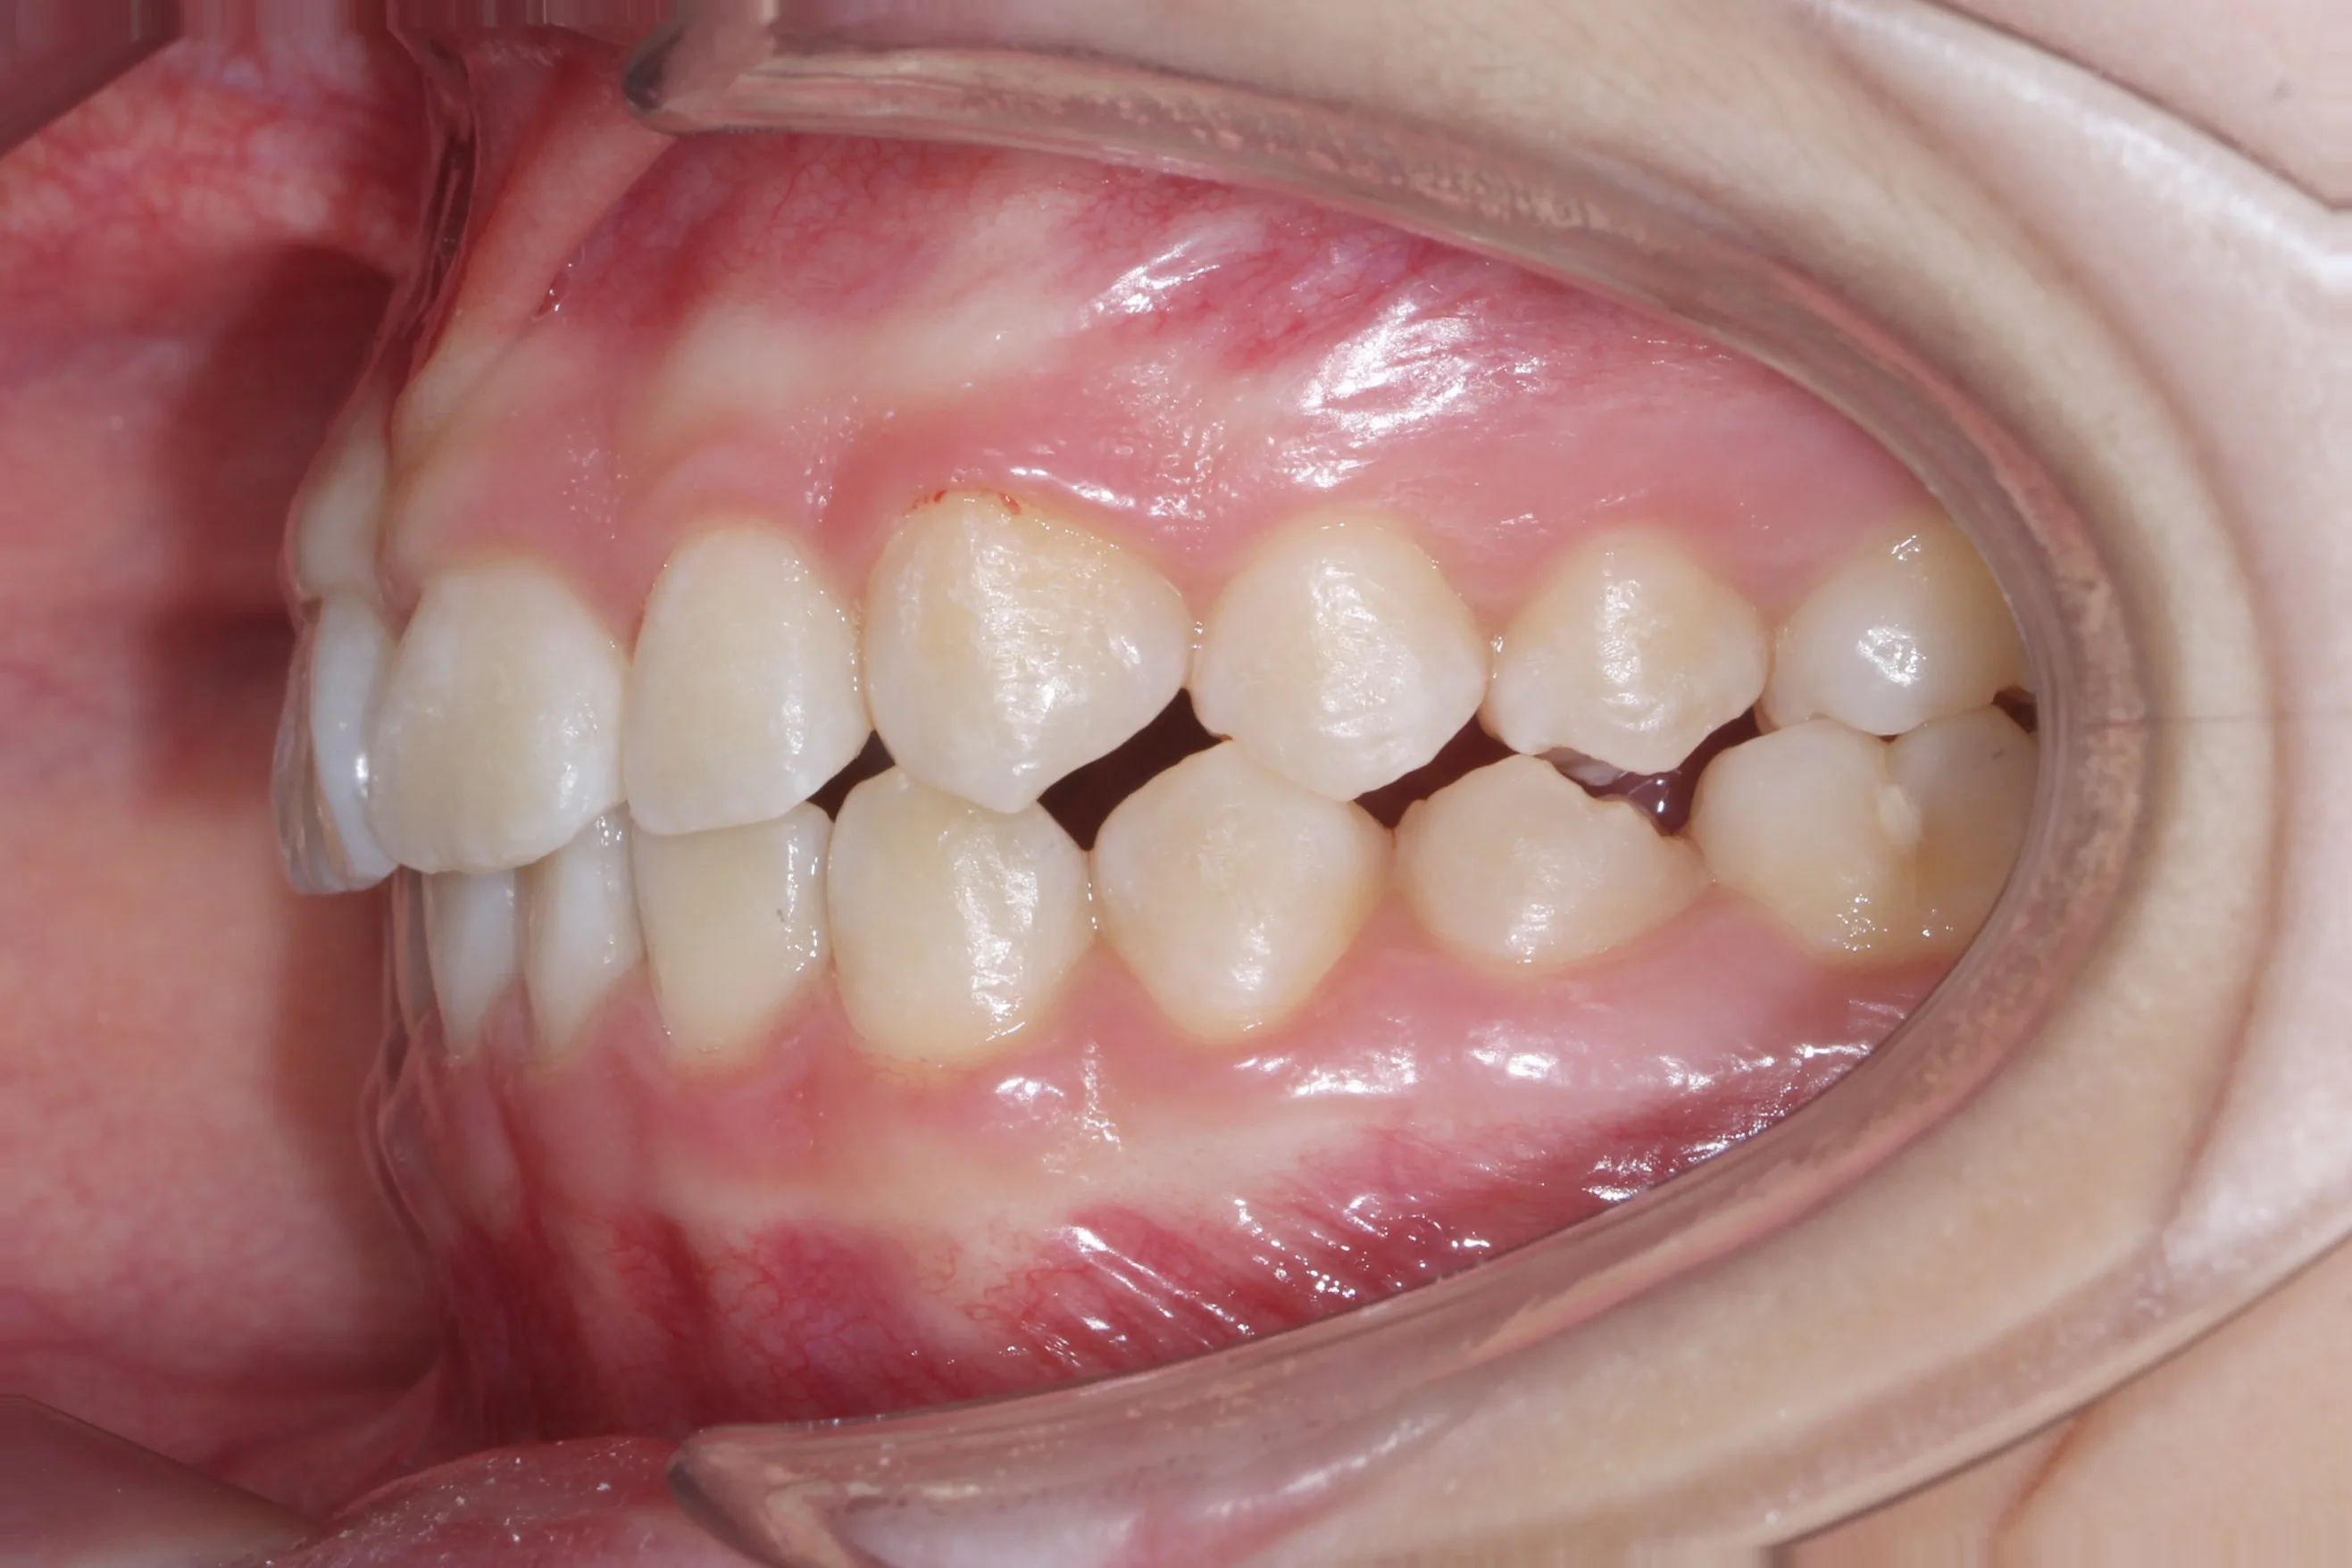

만 11세 환자분께서 튀어나온 앞니와 다물어지지 않는 입술 때문에 내원하셨습니다. 검진 결과 상악 전돌을 동반한 2급 부정교합(Class II malocclusion) 상태였으며, 아래턱의 성장이 다소 부족하여 골격적인 조화가 필요한 상황이었습니다.

이번 치료에는 인비절라인 퍼스트(Invisalign First)에 하악 전방 견인(Mandibular Advancement, MA wing)을 추가하여 치료를 진행하였습니다. 성장기라는 시기적 특성을 적극 활용하여 아래턱의 점진적인 성장을 유도하고, 과도한 상악 전치부 돌출을 개선하는 데 치료의 핵심 전략을 두었습니다.

2년 7개월의 치료 과정을 거치며 환자분의 협조도 덕분에 안모 프로파일과 교합이 안정적으로 개선되었습니다. 성장기라고 해서 무조건 교정이 어려운 것은 아닙니다. 적절한 시기에 맞춤형 장치를 선택한다면 골격적 불균형을 효과적으로 바로잡을 수 있습니다.